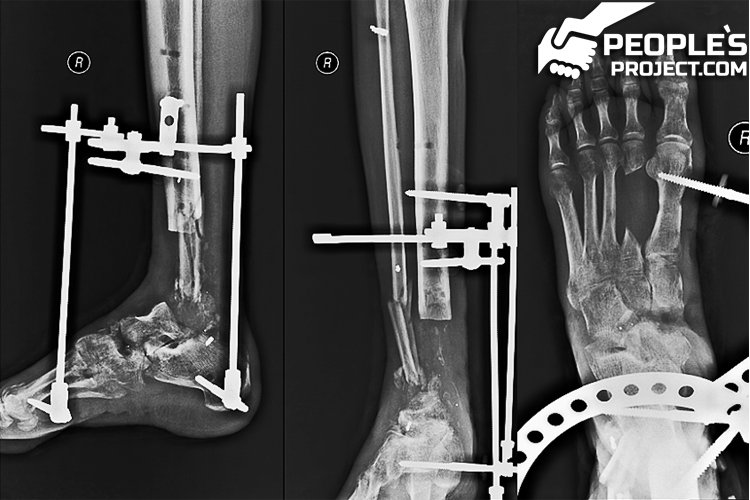

Один із тяжкопоранених бійців через два роки страждань нарешті став на ноги

Поранений боєць став на ноги